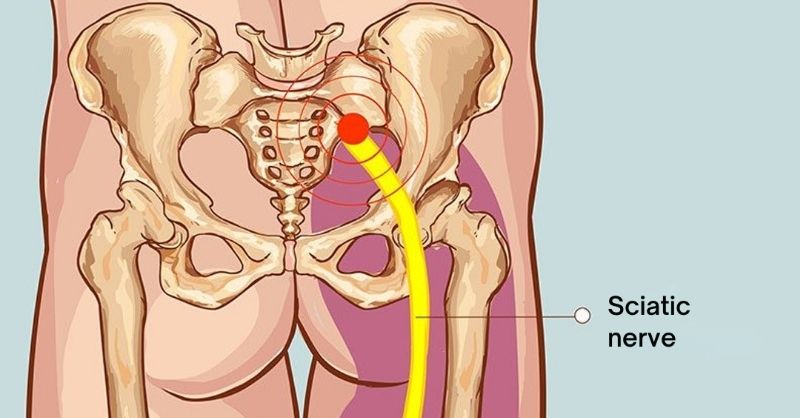

4 Exercises to Stretch the Piriformis and End Sciatica and Lower Back Pain

When pain travels from the lower back down the leg, sciatica is often the culprit. This common condition typically results from nerve irritation or compression, with one muscle...